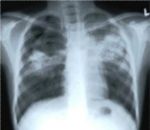

1)Могут разве только на основании рентгена поставить диагноз?Если все анализы в норме,кашля нет,диаскин тест отриц,мокрота отриц.!

Просто преживаю сильно!!!Можно просто по ренгену назначть диагноз?!И получать таблетки вообще в своей поликлинике!!Очень много противоречий,с такой болезнью!

В августе проходил флюорографию, обнаружили затемнения, пролечили от пневмонии, без изменений, в итоге поставили диагноз очаговый туберкулез верхней доли левого легкого. Мокрота не выделялась абсолютно у меня(я не курю и не курил никогда), послали на бронхоскопию, результат отрицательный. Назначили лечение 2 месяца интенсивной фазы 4 препарата, и потом 4 месяца поддерживающей. Лечение назначили сразу на домашнем стационаре, в поликлинику не положили, сказали легкая форма, начальная стадия и нет бактериовыделения. 2 месяца принимал препараты, самочувствие хорошее, побочных эффектов не было, кашля нет. По окончании 60 доз назначили рентген и бронхоскопию. Бронхоскопию делали в другой поликлинике, пришел результат положительный, рентген с положительной динамикой. Врач сказал продлить интенсивный курс до 90 доз и лечиться дальше на дневном стационаре.